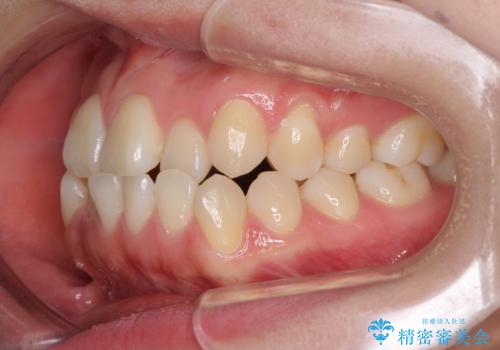

- 前歯のデコボコとクロスバイトを気にして来院された患者様です。

骨格的に下顎が前方位の受け口傾向であり、それが原因でクロスバイトとなっていました。

なお、右奥の歯が180度回転した状態で萌出しており、こちらは改善困難なため、そのままの向きで配列することとしました。